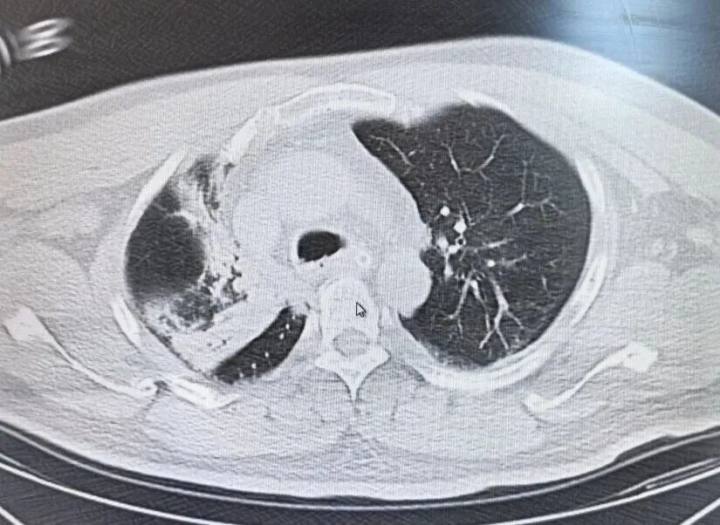

▲肺部CT提示吸入性肺炎(医院供图)

入院时,吴先生已经意识模糊,气道被呕吐物完全堵塞。血氧饱和度持续走低,生命危在旦夕。急诊医生立即予气管插管、输液等抢救措施;同时完善CT检查,提示“吸入性肺炎”,立即转入ICU救治。